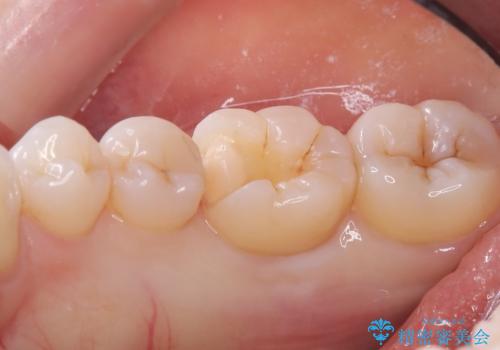

- 主訴:右下の奥歯がたまに冷たい物や甘いものでしみる

右下6番目の歯に大きめのう蝕を認め、形態の再現性を考えインレーでの治療となりました。

右下6の近心にう蝕が認められう蝕の範囲が大きかったため、歯冠形態の再現性の高いインレーでの修復とし、材質は審美性、清掃性に優れたセラミックを選択しました。